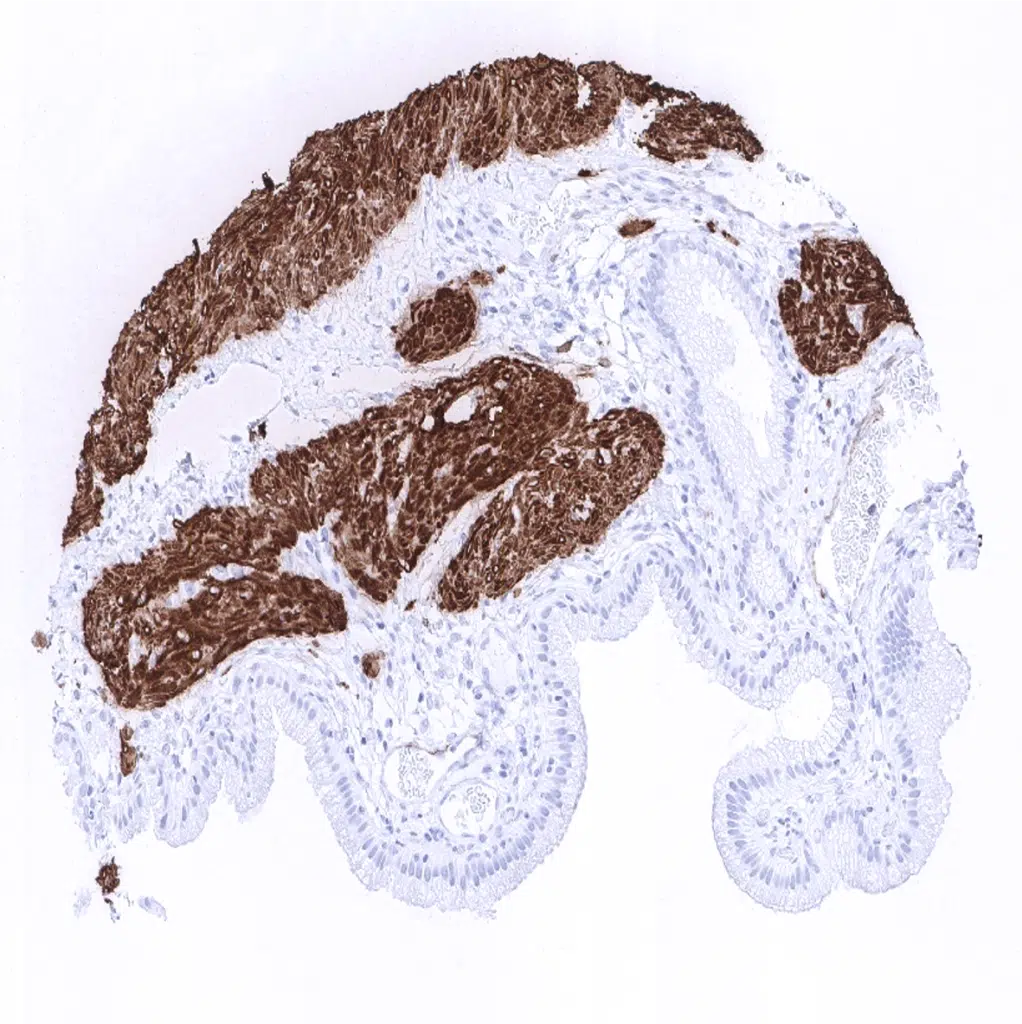

Calponin 1 antibody [MSVA-455R] HistoMAX

Rectum, mucosa